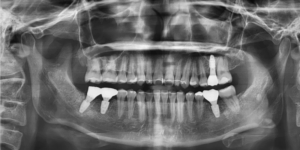

전체적인 치열이 고르지 않은 상황이었고

상하좌우 4개의 매복사랑니가 있었으며

군데군데 이미 충치가 깊어서 뿌리만

남아있는 치아가 여러개 있었습니다.

임플란트 보철까지 완성한 모습입니다.